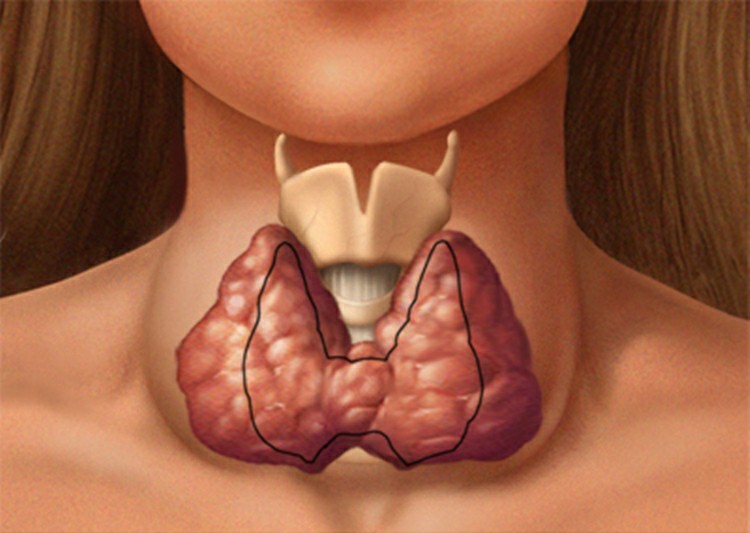

Bócio – O que é, Causas, Sintomas e Tratamentos que muitos desconhecem. Além disso, o Bócio (GOI-tur) é um aumento anormal da glândula tireoide. Sua tireoide é uma glândula em forma de borboleta localizada na base do pescoço logo abaixo da maçã de Adam. Embora o Bócio geralmente sejam indolores, um Bócio grande pode causar tosse e dificultar a ingestão ou respiração. A causa mais comum do Bócio em todo o mundo é a falta de iodo na dieta. No brasil, onde o uso de sal iodado é comum, um Bócio é mais freqüentemente devido à sobre ou subprodução de hormônios tireoidianos ou a nódulos que se desenvolvem na própria glândula.

O tratamento depende do tamanho do Bócio, dos sintomas e da causa subjacente. Bócio pequenos que não são visíveis e não causam problemas normalmente não precisam de tratamento.

Causas de Bócio: Sua glândula tireoidiana produz dois hormônios principais – tiroxina (T-4) e tri-iodotironina (T-3). Esses hormônios circulam na corrente sanguínea e ajudam a regular seu metabolismo. Eles mantêm a taxa em que seu corpo usa gorduras e carboidratos, ajudam a controlar a temperatura do seu corpo, influenciam a freqüência cardíaca e ajudam a regular a produção de proteínas.

Sua glândula tireoidiana também produz calcitonina – um hormônio que ajuda a regular a quantidade de cálcio no sangue. Sua glândula pituitária e seu hipotálamo controlam a taxa em que esses hormônios são produzidos e liberados. O processo começa quando o hipotálamo – uma área na base do seu cérebro que atua como um termostato para todo o sistema – sinaliza sua glândula pituitária para fazer um hormônio conhecido como hormônio estimulador da tireoide (TSH).

Sua glândula pituitária – também localizada na base do seu cérebro – libera uma certa quantidade de TSH, dependendo da quantidade de tiroxina e T-3 no seu sangue. Sua glândula tireoidiana, por sua vez, regula a produção de hormônios com base na quantidade de TSH que recebe da glândula pituitária.

Ter um Bócio não significa necessariamente que sua glândula tireoide não está funcionando normalmente. Mesmo quando está ampliado, sua tireoide pode produzir quantidades normais de hormônios. Pode também, no entanto, produzir muito ou muito pouco tiroxina e T-3. Uma série de fatores podem fazer com que sua glândula tireoide se aumente. Entre os mais comuns estão: